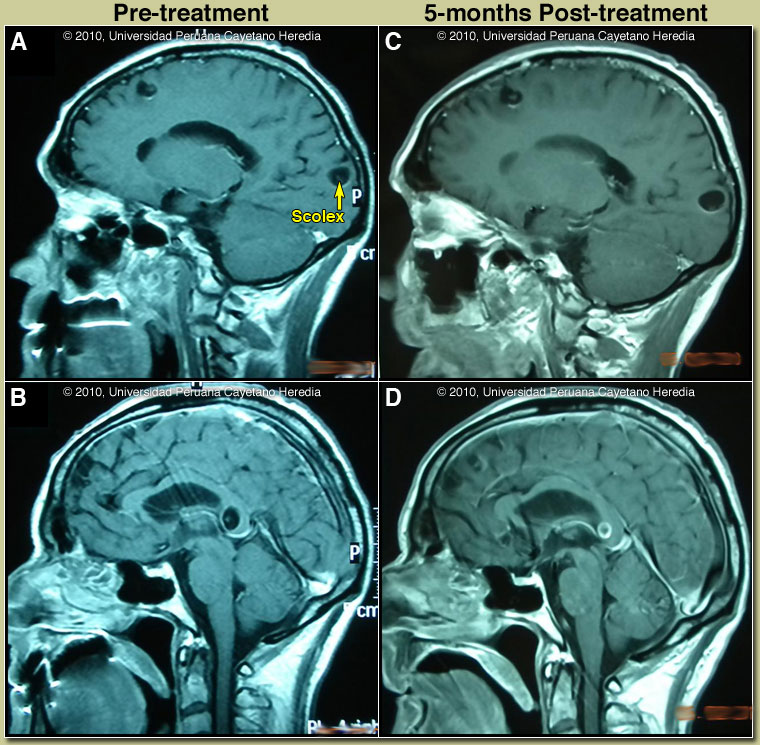

Discussion: The MRIs shown in Images A & B are diagnostic without any further testing; visualization of a fluid filled cyst with a scolex inside [arrow, Image A] is diagnostic. The scolex is the head of the larval T. solium tapeworm. Edema around a dying cyst is often the trigger for onset of seizures in infected individuals. In this case a Western blot was performed and was positive. Fortunately, no intraventricular lesions or signs of intracranial hypertension were seen in this patient, as such cysts are more difficult to manage.

Cysticercosis is infection with the larval stages of the human pork tapeworm Taenia solium. Humans acquire cysticercosis after ingesting eggs of T. solium in material contaminated with feces originating in human tapeworm carriers. Humans that do not eat pork can get cysticercosis. Ingestion of contaminated pork results in humans getting an adult intestinal tapeworm, not cysticercosis. Cysticercosis is common in many developing countries and very common in rural agricultural areas of Perú. In developed countries the long-lived cysticerci are increasingly seen as immigration from affected areas rises. Occasional transmission by tapeworm carriers to those who have never left non-endemic countries is reported. Ingested T. solium eggs hatch in the stomach and are then carried to the muscles and other tissues where the larvae encyst and reach their usual size of about 1 cm within a few months. Clinical manifestations depend on the affected organ but neurocysticercosis causes the most morbidity. The cysticerci seem able to evade the immune system and are thought to remain viable for several years without causing any inflammatory response. Most clinical symptoms are the direct result of inflammatory responses that accompany the eventual cyst degeneration. Epileptic seizures are the primary or sole clinical manifestation in up to 80% of patients. In endemic regions, new onset seizures in teenagers or young adults are most likely due to neurocysticercosis. Cysticerci can also cause symptoms because of mass effect, impingement on a vital structure, or blockage of CSF circulation especially if the cyst is intraventricular. In all cysticercosis patients, seizures need to be managed as per any other form of epilepsy. Treatment of parenchymal neurocysticercosis with antiparasitic drugs such as albendazole is increasingly accepted even when there are few lesions. Albendazole clearly kills the cysts, but may lead to added inflammation and exacerbation of symptoms, which is usually dealt with by empiric concomitant use of steroids. Therapeutic decisions should be based on the number, location, and viability of the cysts. Patients in whom all lesions are already calcified should receive no anti-parasitic treatment. Recent work indicates that long-standing calcified lesions can sometimes provoke peri-lesional edema, which may need treatment with steroids as well as anti-seizure medication. Intraventricular shunting may be necessary if intracranial hypertension results from treatment. Neurocysticercosis is a variable disease and treatment approaches need to be individualized to a large number of differing clinical presentations [Neurology. 2006 Oct 10;67(7):1120-7]. Our patient was treated with albendazole 15mg/kg/d for one-month plus prednisone 1mg/kg/d tapering the dose progressively for a total duration of one month, and phenytoin. After discussion with Gorgas Course professor and consultant Hector Hugo-García, the duration of treatment beyond the standard 8 days was undertaken, based on the proximity of one lesion to the 3rd ventricle [Image B]. He tolerated the therapy but his headache failed to resolve. Repeat MRI 5 months later [Images C & D] showed good involution of the peri-ventricular lesion but little effect of treatment on the parenchymal lesions. A further course of treatment was decided after follow-up consultation with Dr García. His experience is that a significant resolution in the size of many lesions should have occurred in the 5-month follow-up period. Not achieving that is an indication for longer duration of treatment and perhaps for combination therapy. Our patient was started on a combination of albendazol 15mg/kg/d plus praziquantel 50mg/kg/d and steroids, with plan to give these drugs for at least one month; this regimen is currently being evaluated in a phase II clinical trial compared with albendazole.